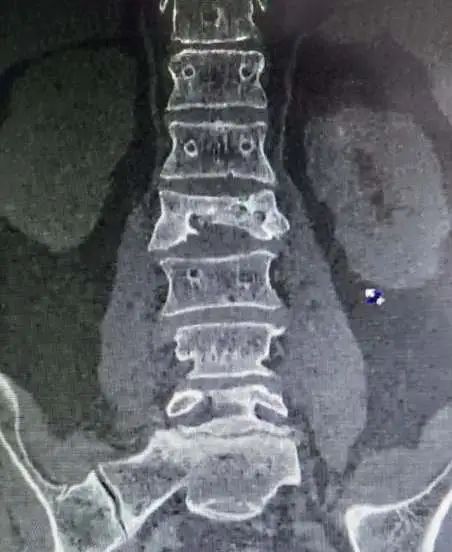

终于在令人焦急地等待后,检查结果终于出来了:

腰椎骨折!

这绝不是小事,一个不小心,就会造成终生的遗憾!